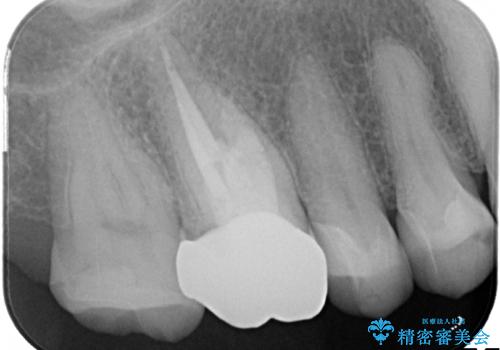

金属だらけの奥歯 根管治療のやり直しとセラミック化

- 神経のある歯を先にセラミック修復し、その後根管治療のやり直しを行う

→最終的にクラウンを製作し、きれいな奥歯を獲得する

神経の無い歯のクラウン(かぶせ物)は、根管治療を顕微鏡下でしっかりとやり直し、その後に土台の築造とかぶせ物の製作を行うことで今後問題が生じる可能性を可及的に低くできます。

かぶせ物の種類:Bellezza